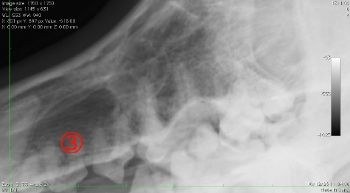

画像の丸で囲ってある部分に破折したファイルが認められます。

根管の位置を実際に想像してみることが大切です。根管のアクセスした部位からはより遠位であることがわかります。デンチンの厚さを想像しながら探っていきます。またこの位置にはもう一本の根管が存在するために削っていくこと、探すことに専念しすぎるとパーフォーレーションを起こし、もう一本の根管口を見失う可能性があります。ですから、折れたファイルを探すことへの焦りを捨て、まずはもう一本の根管拡大を終了させ、確実にその根管をとらえられるようにすることが大切です。

かなり削りましたが、この状態で初めて破折ファイルを目視することが可能となります。レントゲンではわかりやすいのですが、およそ0.5~0.8mmを見ることが可能です。

それでは今回入れたファイルと以前ファイルを入れられた状態の角度を比較するために画像を重ねて表示してみましょう。

正しくファイルを入れた方向と最初にファイルを破折させた角度を見ると、折れたファイルはかなじ前方から根管口に入っていることがわかります。このような現象は、最初に根管へアクセスする際、歯をあまり削らずに行おうとしたために、急角度にファイルが曲がって根管口へ突入したために破折したことがわかります。下記に示すように、青でファイルを挿入すると折れますが、黄色の位置から挿入すると折れることはありません。根管に対してできる限りまっすぐにいれることのできるアクセスを行うことが重要です。